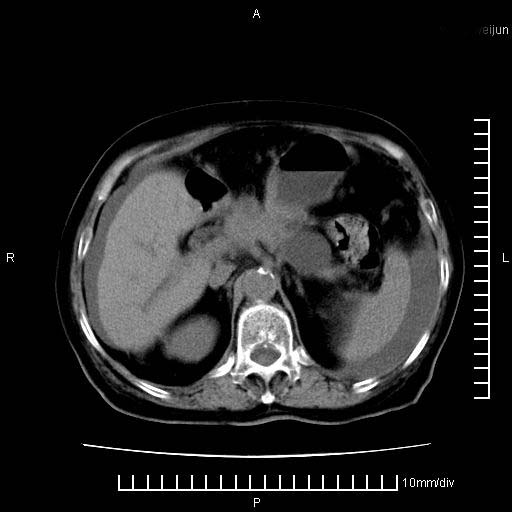

上腹疼痛月余,外院核磁诊断胰腺癌。现临床示右下腹可明显触及包块,可片子上怎么没有看到?

1.胰腺颈体部癌。

胰腺体部癌累及周围器官,腹膜、粘连

1。胰腺ca伴腹膜腔转移

2。肝左叶低密度灶,考虑转移可能

胰腺体部癌累及周围器官,腹膜、粘连,临床摸到的可能是粘的组织

支持胰腺癌肝内转移,腹水改变。

胰腺结构模糊,胰尾部见囊性包块,周围脂肪密度增高,左肾前筋膜增厚,胸水、腹水。不符合胰腺ca伴腹膜腔转移。考虑胰腺炎伴假性囊肿形成、胸腹腔积液。

1、考虑胰腺癌伴腹膜腔转移,胸腹水。

2、肝脏转移可能。

1)考虑胰腺癌并胰腺假性囊肿形成。2)肝内低密度灶,不排除转移。3)右肾盂积水。4)腹水。5)右侧胸腔积液并右肺下叶部分膨胀不全。

考虑胰腺ca伴腹膜腔转移、肝左叶转移、右肾积水。右胸腔积液。